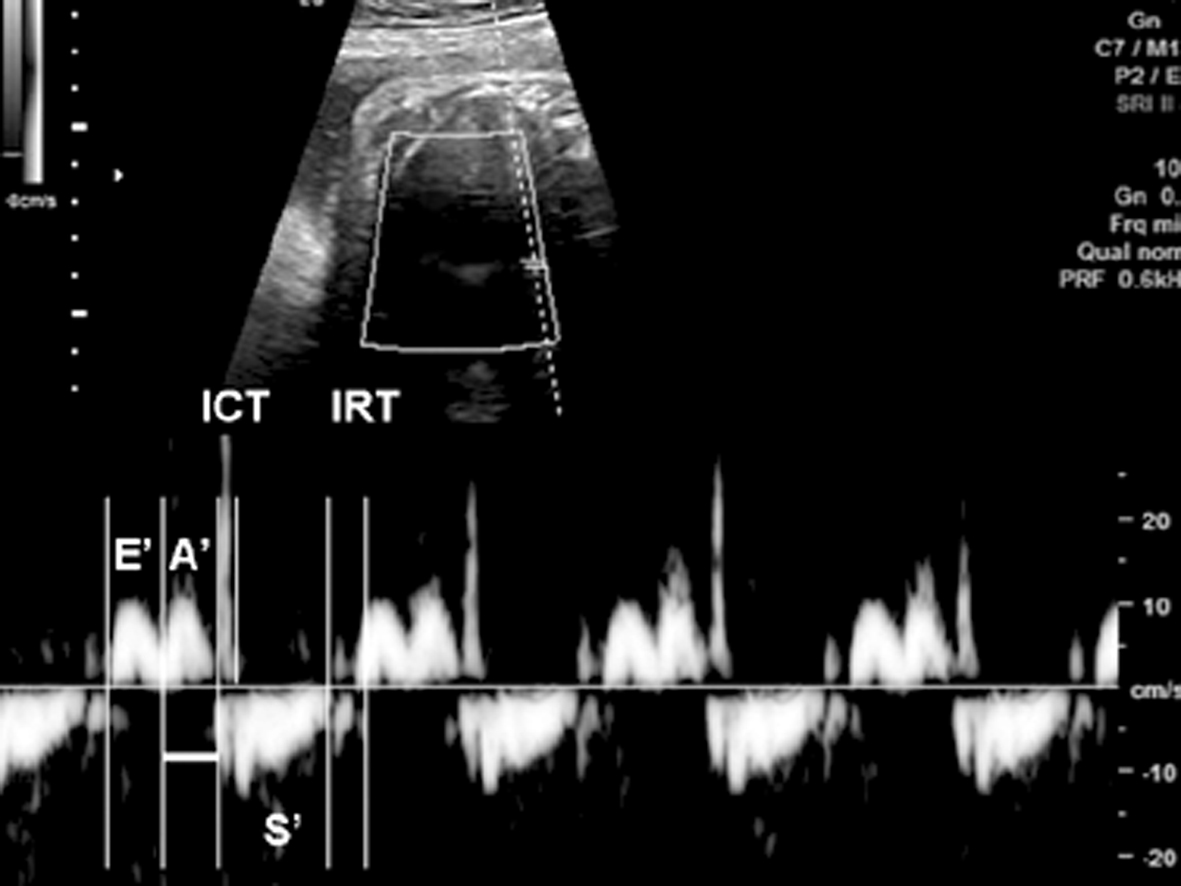

组织多普勒超声心动图是目前最新的用于诊断胎儿心律失常的方法。有文献报道称其优于M型及脉冲多普勒超声心动图,在同一心动周期内可同时记录心脏多个部位的活动,其更能有效地确定心脏的节律和房室间隔。比如在组织多普勒超声心动图中,心房收缩开始到等容收缩期开始的间隔更接近于胎儿心电图的PR间期(图3)。但组织多普勒超声心动图对超声机器配置要求较高,应用还不广泛,其准确性还需进一步考察。

图3正常胎儿频谱组织多普勒图